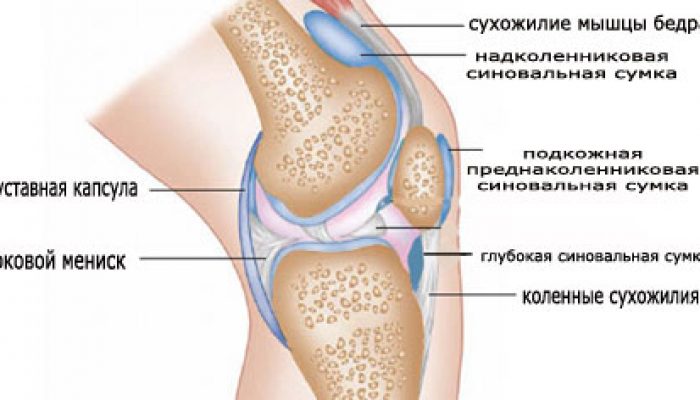

Суставная Жидкость и Головка Сустава: Обзор и Здоровье